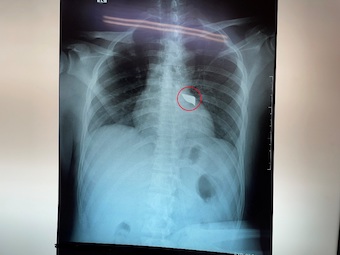

Tình trạng lúc nhập viện, bệnh nhân H. tỉnh, niêm hồng, than đau lưng, khó thở nhẹ với vết thương lưng thành ngực sau cạnh trái cột sống đoạn ngực 4-5 rỉ máu, còn dị vật, không tê yếu chi, dấu hiệu sinh tồn ổn định.

Các bác sĩ khoa Cấp cứu nhanh chóng xử trí cấp cứu và thực hiện các xét nghiệm, siêu âm, chụp Xquang tim phổi thẳng, chụp cắt lớp vi tính lồng ngực… Việc hội chẩn phẫu thuật được ê-kíp bác sĩ khẩn tiến hành và thống nhất phương án xử lý thám sát vết thương và lấy dị vật cấp cứu.

Sau 90 phút phẫu thuật, ê-kíp phẫu thuật gồm: Bs.CK2 Trần Văn Minh – Phó Trưởng, khoa Ngoại Thần kinh, Bs. Nguyễn Châu Thanh, Bs.CK1 Nguyễn Văn Vĩnh – Khoa Phẫu thuật – Gây mê hồi sức đã lấy thành công mũi dao dài 5x2cm ra ngoài.

Theo Bs.CK2 Trần Văn Minh, may mắn là trường hợp này mũi dao chưa gây vết thương tủy sống, nếu tổn thương tủy sống bệnh nhân sẽ có rối loạn cảm giác, rối loạn vận động, liệt tủy không hoàn toàn với các biến chứng dò dịch não tủy, nhiễm trùng, áp xe, viêm màng não tủy.

Bác sĩ khuyến cáo, với những trường hợp tương tự điều đặc biệt lưu ý là không được tùy tiện rút vật xuyên thấu ra khỏi vết thương tại hiện trường tai nạn hoặc ngay cả trong phòng cấp cứu, mà cần được đánh giá bằng các công cụ chẩn đoán hình ảnh như siêu âm, xquang, chụp cắt lớp vi tính trước để có thể lường được mức độ tổn thương và các nguy cơ tai biến có thể xảy ra khi rút vật xuyên thấu.